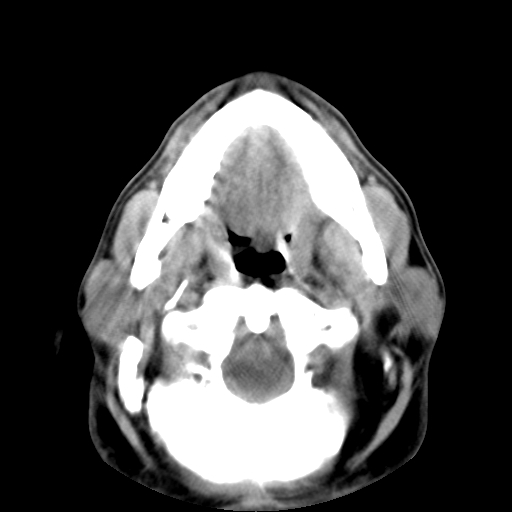

标题: CT24019:男,45岁,发现颈部肿物5个月。 [打印本页]

标题: CT24019:男,45岁,发现颈部肿物5个月。

男,45岁,发现颈部肿物5个月,彩超示:双侧颈部及下颌部软组织增厚。

考虑双侧颈项部良性对称性脂肪增多症。